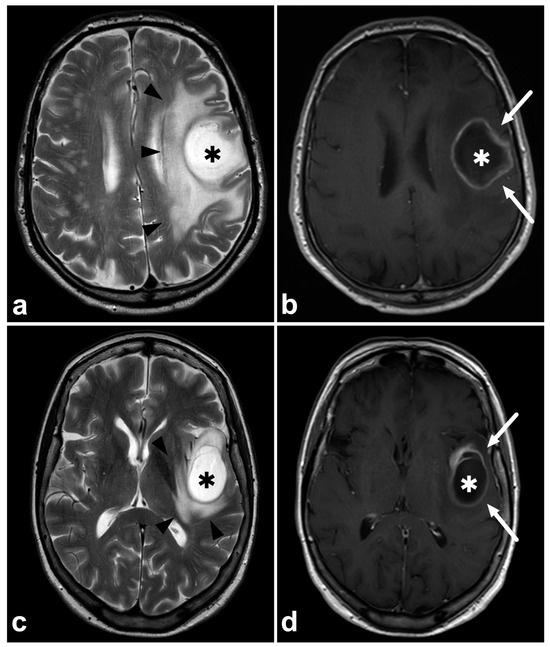

Correct tentative tumor type characterization reduces unnecessary steps in the definitive diagnostic pathway. A suspicion of metastasis or lymphoma should lead to a search for the primary tumor and determination of disease extent, while in gliomas, further imaging is not routinely needed. Figure 2 demonstrates two examples of glioblastomas, of which another one was initially suggested to represent a solitary metastasis. This led to unnecessary thoracoabdominal computed tomography to search for a primary tumor. Unnecessary scans mean increased expenses, radiation exposure, and delayed treatment. Regardless, knowing the difficulties in discriminating glioma from metastasis based on MRI only, the threshold for performing thoracoabdominal CT in case of newly detected brain tumors must remain low.

Figure 2. (a) Patient 1, axial T2-weighted MRI, (b) Patient 1, axial gadolinium-enhanced T1-weighted spin-echo MRI, (c) Patient 2, axial T2-weighted MRI, (d) Patient 2, axial gadolinium-enhanced T1-weighted spin-echo MRI. Two patients with a histopathologically confirmed glioblastoma. Patient 1 (upper row) was initially suggested to have a solitary cerebral metastasis (asterisks), primarily because of the rapid appearance of the tumor (the previous MRI six months earlier was unremarkable) and because of the extensive edema surrounding the tumor (black arrowheads). Patient 1 underwent a thoracoabdominal CT scan to detect the primary tumor and other metastases. Patient 2 (lower row) was initially suggested of having a glioblastoma (asterisks) and the patient was immediately directed to the neurosurgeon without unnecessary steps. The diagnosis of glioblastoma was later confirmed histopathologically. Both tumors demonstrate a homogenous, probably necrotic center (asterisks) surrounded by a gadolinium-enhancing rim (white arrows). The enhancing rim is surrounded by a T2-hyperintense zone consisting of poorly delineated tumor infiltration and vasogenic edema, sometimes inseparable from each other with conventional clinical imaging. Brain metastasis often represents very similar MRI findings compared to glioblastomas.